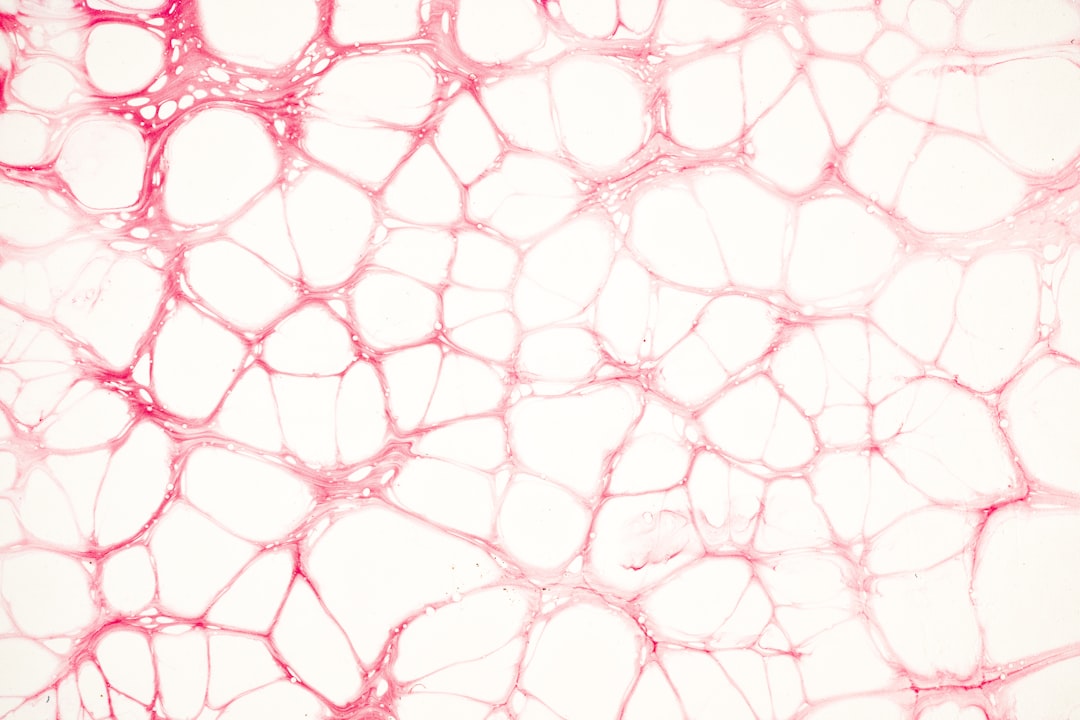

여기서 한 가지 재미있는 사실은, 피부의 콜라겐 생산량은 나이가 들어감에 따라 감소한다는 점입니다. 그러므로 파이토프리콜라겐 같은 보충제를 섭취하는 것이 피부 건강을 유지하는 데 매우 유용할 수 있습니다. 수많은 연구와 실험을 통해 이러한 효과가 입증되었고, 이에 따라 많은 사람들이 이를 통해 아름다움을 유지하고 있습니다. 이 점이 이 글에서 계속해서 다룰 주제이니 기대해 주세요!

두 번째로, 파이토프리콜라겐은 관절 건강에도 도움을 줄 수 있습니다. 다양한 변형형 관절염 환자들을 대상으로 한 연구에서, 이 성분이 관절의 유연성을 개선시키고 통증을 감소시킨다는 결과가 나왔습니다. 특히 운동을 많이 하는 분들이 이렇게 효과를 경험할 수 있습니다. 이번에는 이와 관련된 구체적인 사례를 함께 살펴보면 좋겠네요!